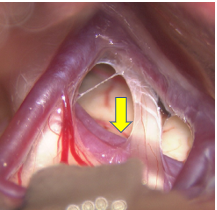

40代 男性 下垂体腫瘍

頭痛の精査でMRIを撮影しましたところ、脳底部の脳下垂体に腫瘍がみられ、視神経を圧迫していました。開頭ではなく、鼻孔から腫瘍を摘出しました。